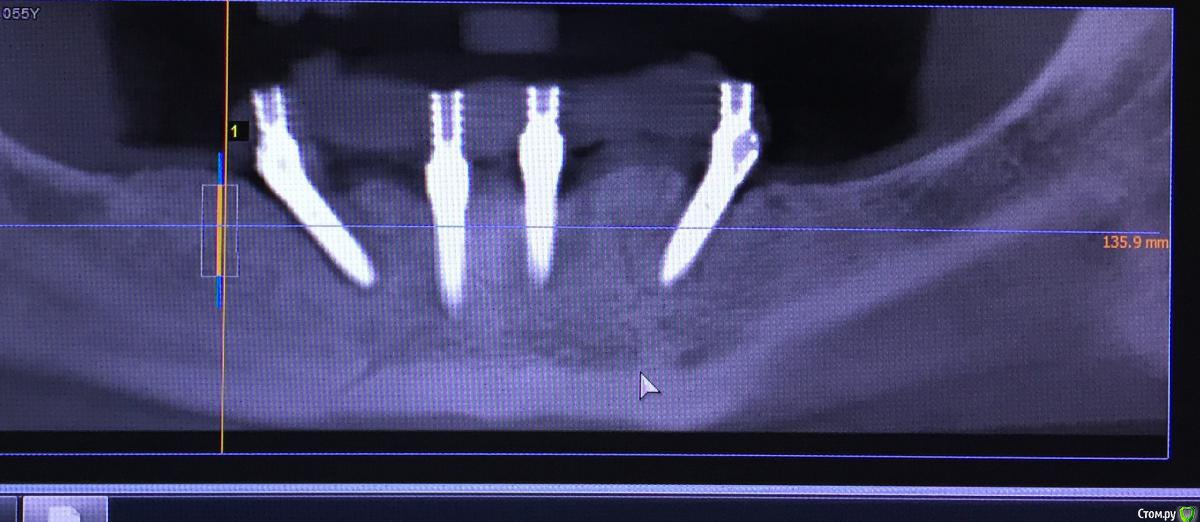

Evikrol Опубликовано 7 октября, 2016 Автор Поделиться Опубликовано 7 октября, 2016 (изменено) Я за изначально не высокий торк и изменение/смещение положения имплантата на ортопедическом протоколе.Которое усугубило точность посадки протеза на фоне гигиены. Думаю стоит просто переставить.Торк был хороший более 50, а вот смещение ортопедической конструкцией возможно. А.Л.Давидян говорил что ортодонтическая нагрузка улучшает итеграцию, разве усилия при не точном протезировании не схоже с влиянием брекетов? ДУмаю рядом поставить 10 мм под прямым углом. место есть Изменено 7 октября, 2016 пользователем Evikrol Ссылка на комментарий

Konrad Опубликовано 7 октября, 2016 Поделиться Опубликовано 7 октября, 2016 (изменено) Торк был хороший более 50, а вот смещение ортопедической конструкцией возможно. А.Л.Давидян говорил что ортодонтическая нагрузка улучшает итеграцию, разве усилия при не точном протезировании не схоже с влиянием брекетов? ДУмаю рядом поставить 10 мм под прямым углом. место естьЕсли могла быть не точность, усилие на винте могло дать крутящий момент силы по типу рычага. Где остальные три были не подвижны. Но это все равно все из разряда предположений. У Вас стоит 45 градусный мультик? Можно поместить дистальнее 11.5, ментальное может наслаиваться, но по факту это будет не важно. Я бы уходил на 17° или 30° в этом случае имплантат будет стоять в полностью интактной костной ткани. А лучше сделать так и ещё добавить один медиальнее от проблемного как Вы и хотели. Будет ол-он-4+1 Изменено 7 октября, 2016 пользователем Konrad Ссылка на комментарий

kriokov Опубликовано 7 октября, 2016 Поделиться Опубликовано 7 октября, 2016 В межментальном четыре параллельных имплантата держат не хуже, чем "оллинфор". Девять лет отдаленных результатов и минимальный процент проблем. Конструкция от 6 до 6 работают отлично.диаметр имплантатов такой же как в "оллинфо" от 4.3 мм? Ссылка на комментарий

Evikrol Опубликовано 7 октября, 2016 Автор Поделиться Опубликовано 7 октября, 2016 Что если просто удалить и поставить так? 1 Ссылка на комментарий